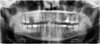

Cas 8 : MALPOSITIONS DENTAIRES ET EXTRACTION D'UNE INCISIVE MANDIBULAIRE

Traitement par aligneurs transparents réalisé chez une patiente de 35 ans. La patiente présentait un encombrement à l’arcade mandibulaire important. Il a été choisi d’extraire une incisive mandibulaire. Le traitement a duré 18 mois.

Traitement par aligneurs transparents réalisé chez un homme d’une trentaine d’années, le motif de de consultation portait sur les malpositions importantes, notamment à l’arcade mandibulaire. Le traitement a nécessité l’extraction d’une incisive mandibulaire.

La durée du traitement a été de 18 mois. En fin de traitement afin d’améliorer l’esthétique du sourire les composites antérieurs été refaits, ainsi que des coronoplasties par apport afin d’harmoniser la forme des incisives ( soins réalisés par une consœur).

Traitement réalisé chez une patiente de 50 ans, présentant un encombrement mandibulaire et les agénésies de 12 et 22, les canines maxillaires ayant pris la place des incisives latérales. Le dentiste traitant lui avait proposé de corriger les malpositions par facettes, mais la patiente souhaitait trouver une solution plus conservatrice. L’orthodontie a permis la correction des malpositions, et le savoir-faire d’une consœur a permis de maquiller les canines maxillaires en incisives et d’harmoniser les bords libres des incisives centrales qui avaient été usés.

Traitement par aligneurs transparents réalisé chez un patient de 50 ans. Le patient présentait un encombrement à l’arcade mandibulaire important et un articulé inversé de la canine mandibulaire gauche. Il a été choisi d’extraire une incisive mandibulaire. Malgré l’extraction de cette incisive, l’occlusion finale est parfaitement équilibrée.

Traitement par aligneurs transparents réalisé chez un patient de 47 ans. Le patient présentait un encombrement à l’arcade mandibulaire important et un articulé inversé de la canine mandibulaire droite. Il a été choisi d’extraire une incisive mandibulaire qui était mobile à cause d’une lésion parodontale. Le traitement a permis d’obtenir une occlusion fonctionnelle, de corriger les malpositions, de supprimer les contacts traumatiques, facteurs aggravant de la maladie parodontale et bien sûr de rétablir l’esthétique du sourire.